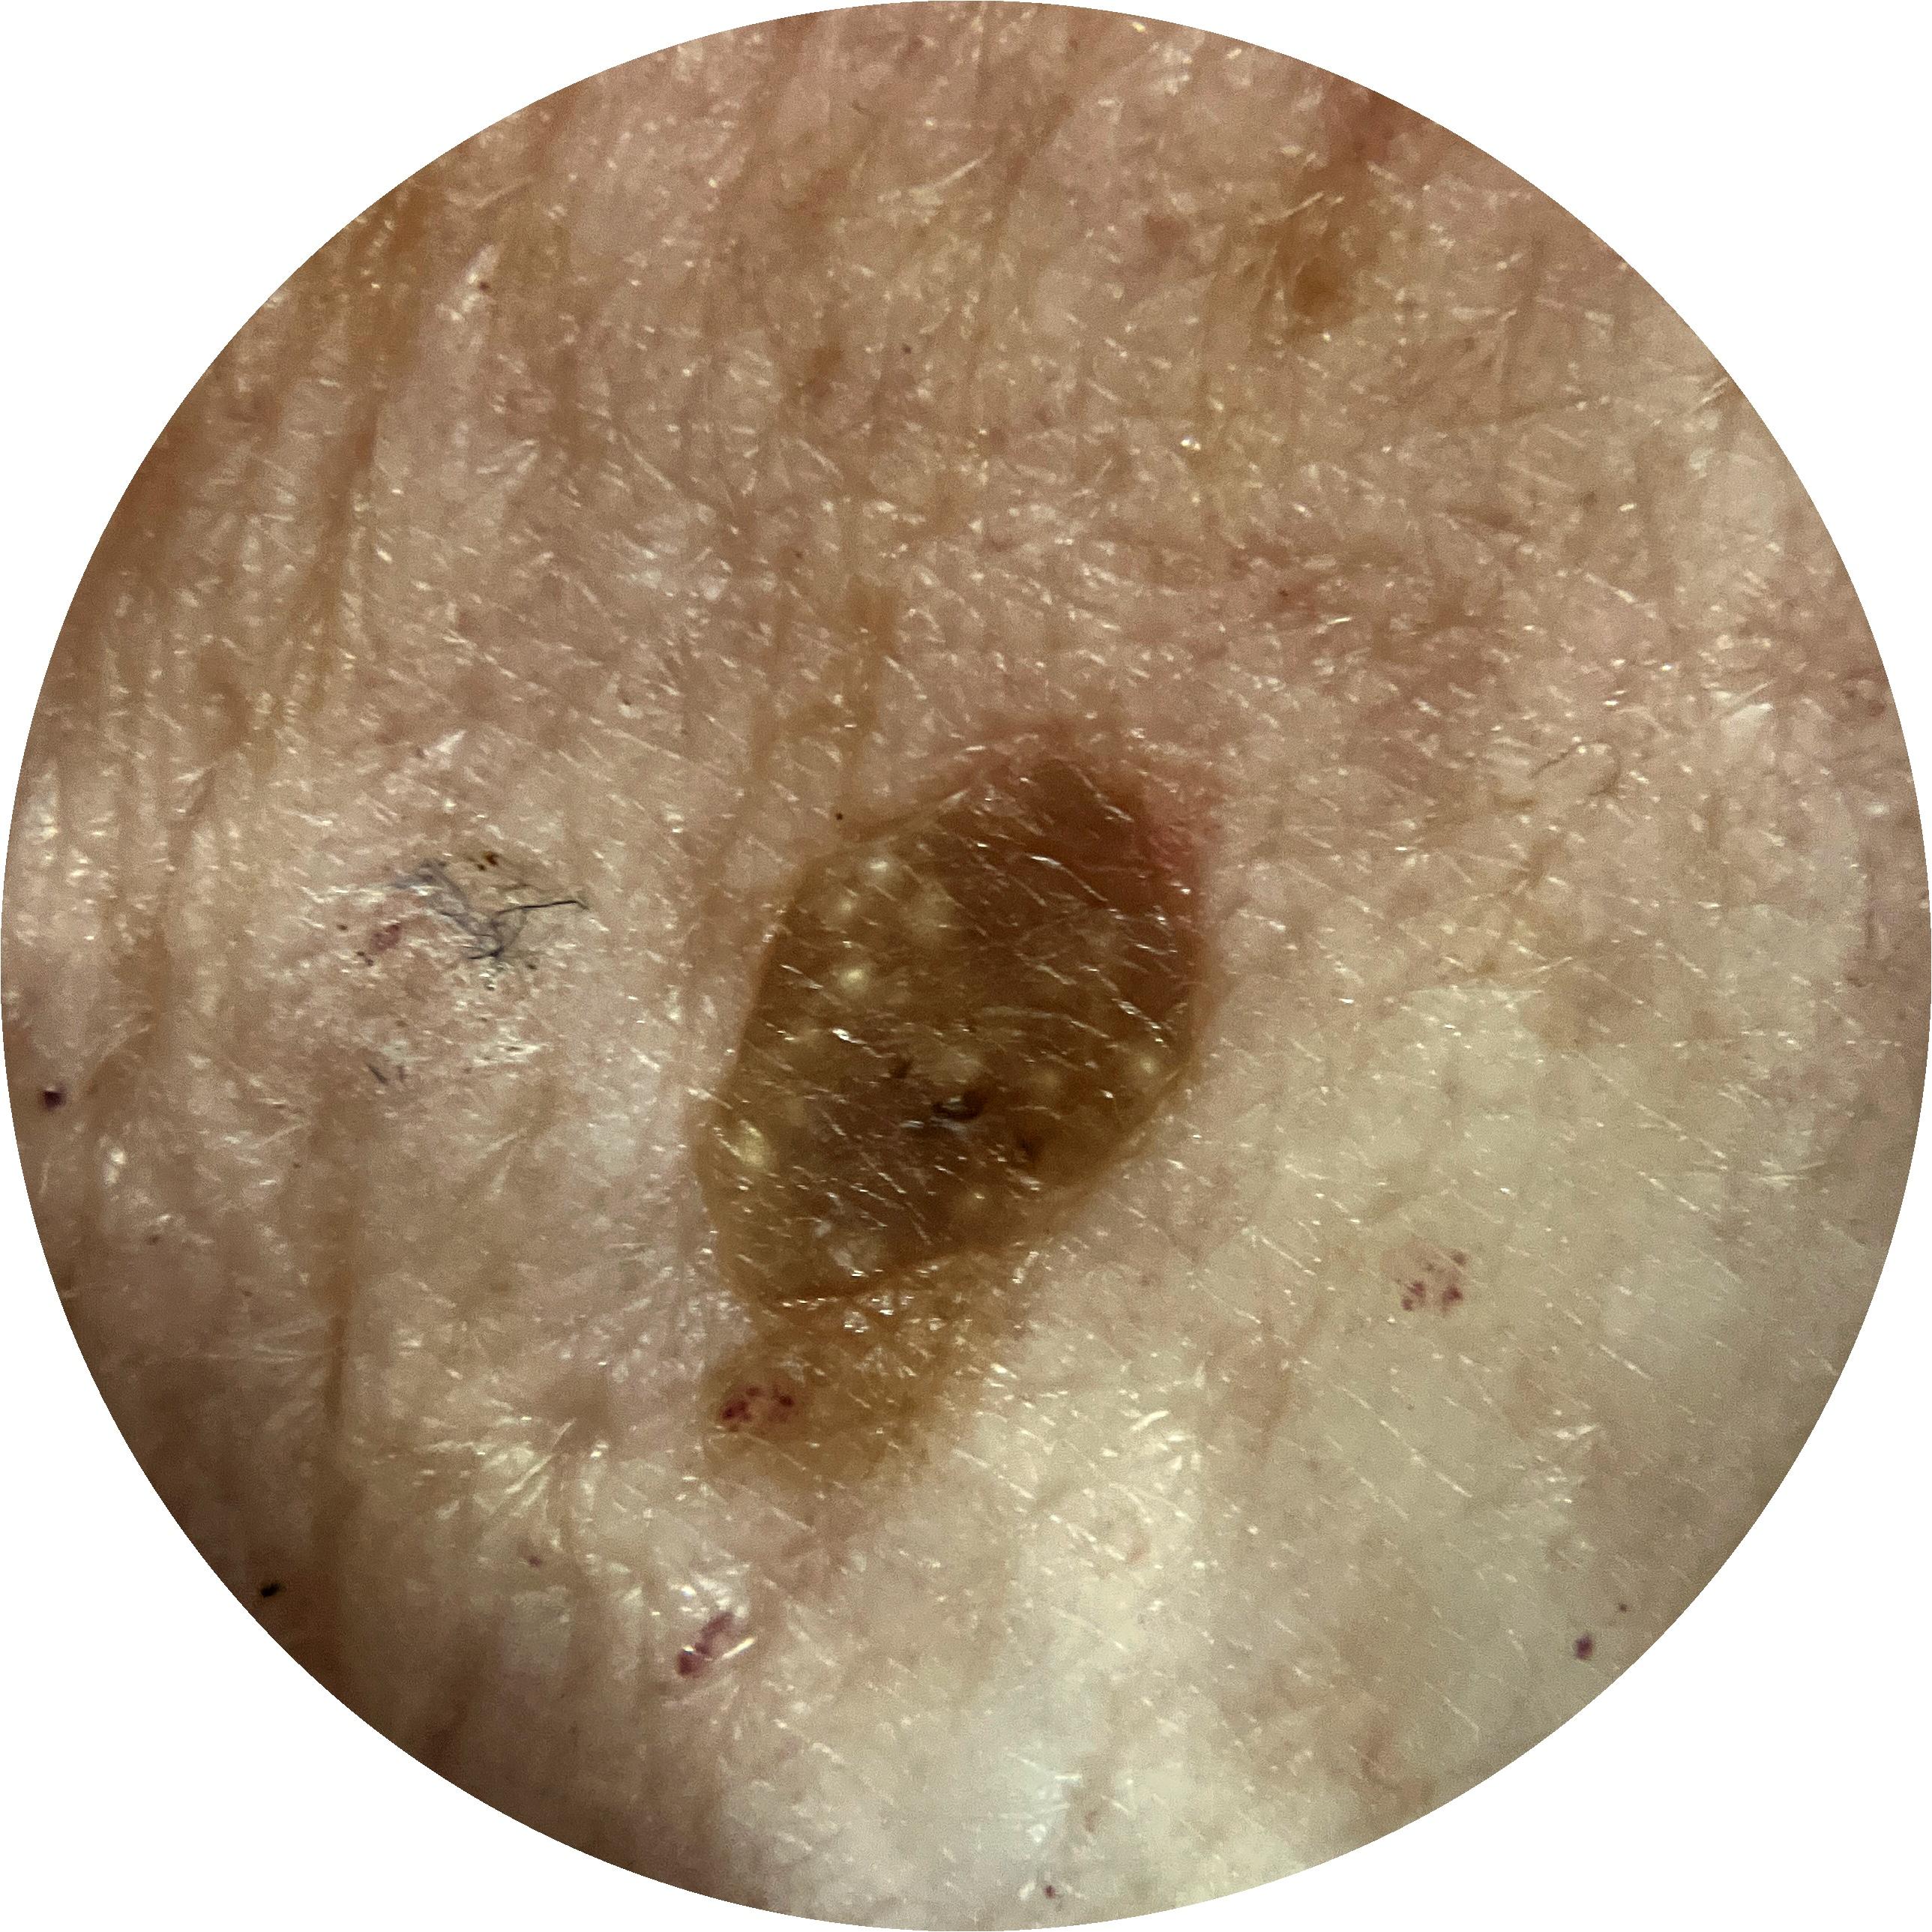

ISIC_8917580

Clinical

Field Value

acquisition_day 361

age_approx 60

anatom_site_1 Lower extremity

anatom_site_general lower extremity

concomitant_biopsy False

diagnosis_1 Benign

diagnosis_confirm_type single image expert consensus

family_hx_mm True

image_manipulation instrument only

image_type dermoscopic

lesion_id IL_4139461

patient_id IP_1989106

personal_hx_mm True

sex male